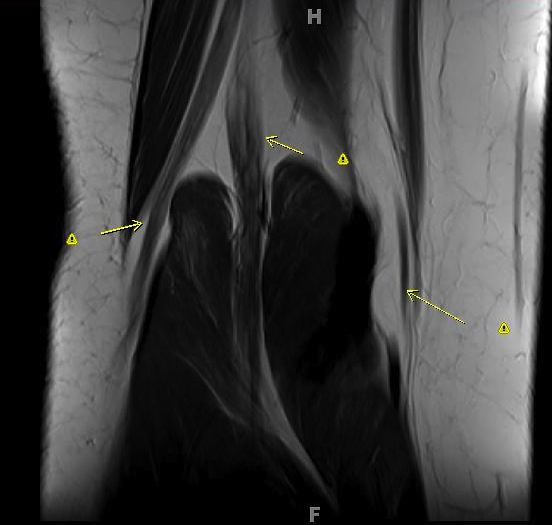

Figure 3 for case Charcot Marie Tooth Type 1a

Figure 3